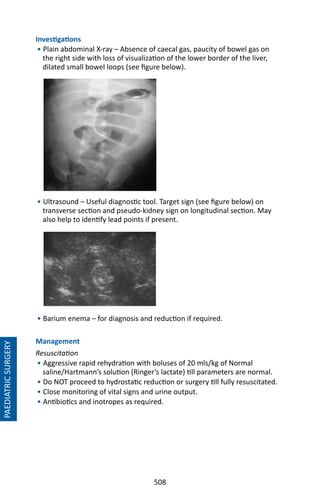

• 534.

521 Chapter 99: NeonatalSurgery OESOPHAGEAL ATRESIA WITH OR WITHOUT A TRACHEO-OESOPHAGEAL FISTULA Presentation • Antenatal: polyhydramnios, diagnosed on ultrasound. • “Mucousy” baby with copious amount of secretions. • Unable to insert orogastric tube. • Respiratory distress syndrome. • Aspiration pneumonia and sepsis. Problems • Oesophageal Atresia: Inability to swallow saliva with a risk of aspiration pneumonia. • Tracheo-oesophageal fistula: Reflux of gastric contents, difficult to ventilate. • Distal obstruction: If present and the baby is ventilated, prone to perforation of bowel. • Prematurity: If present, associated problems. Management • Evaluation for other anomalies/problems e.g. cardiac, intestinal atresias, pneumonia. • Suction of the upper oesophageal pouch: A Replogle (sump suction) tube should be inserted and continuous suction done if possible. Other- wise, frequent intermittent suction (every 10-15 minutes) of oropharynx is done including throughout the journey to prevent aspiration pneumonia. • Ventilation if absolutely necessary. • Fluids - Maintenance and resuscitation fluids as required. • Position - Lie the baby horizontal and lateral or prone to minimise aspiration of the saliva and reflux. • Monitoring – Pulse oximetry and cardiorespiratory monitoring. • Keep baby warm. • Refer to nearest centre with neonatal and paediatric surgical facilities PAEDIATRICSURGERY

• 535.

522 CONGENITAL DIAPHRAGMATIC HERNIA Types • Bochdalek:Posterolateral, commonest, more common on left side. • Eventration of the diaphragm. • Morgagni – anterior, retrosternal. Problems • Associated pulmonary hypoplasia. • Herniation of the abdominal viscera into thoracic cavity causing mechanical compression and mediastinal shift. • Reduced and abnormal pulmonary arterial vasculature resulting in persistent pulmonary hypertension of the newborn (PPHN) and reversal to foetal circulation. • High mortality rate (40-60%) associated with early presentation. Presentation • Antenatal: Fluid filled stomach or bowel with/without liver in the left chest cavity. • Mediastinal shift. • Birth: Respiratory distress with cyanosis. • Absent breath sounds on left side, scaphoid abdomen. • Chest X-Ray: bowel loops within the chest and minimal bowel in abdomen. • Late presentation • Left side: Gastrointestinal symptoms- bowel obstruction. • Right side: Respiratory symptoms including recurrent respiratory infections. • Asymptomatic: Abnormal incidental chest x-ray Differential Diagnoses • Congenital cystic adenomatoid malformation. • Pulmonary sequestration. • Mediastinal cystic lesions e.g. teratoma. PAEDIATRICSURGERY Mediastinal shift Bowel in Left chest cavity

• 536.

523 PAEDIATRICSURGERY Management • Evaluation for associatedanomalies and persistent pulmonary hypertension of the newborn (PPHN). • Ventilation - Intubation and ventilation may be required soon after delivery and pre-transport. Ventilation with a face-mask should be avoided. Low ventilatory pressures are to be used. A contralateral pneumothorax or PPHN need to be considered if the child deteriorates. If the baby is unstable or high ventilatory settings are required, the baby should not be transported. • Frequent consultation with a paediatrician or paediatric surgeon to decide when to transport the baby. • Chest tube - If inserted, it should not be clamped during the journey. • Orogastric Tube: Gastric decompression is essential here. A Size 6 or 8 Fr tube is inserted, aspirated 4 hourly and placed on free drainage. • Fluids – Caution required as both dehydration and overload can precipitate PPHN. • May need inotropic support and other modalities to optimize outcome. • Monitoring: Pre-ductal and post-ductal pulse oximetry to detect PPHN. • Position: Lie baby lateral with the affected side down to optimise ventilation. • Warmth. • Consent: High risk. • Air transport considerations. • Referral to the paediatric surgeon for surgery when stabilised. Factors most affecting the outcome • Birth weight ≥ 2kg: Good outcome. • Apgar score at 5 minutes of 7-10: Good outcome. • Size of defect: If primary repair is achieved, 95% survival vs 57% survival in agenesis. • Willford Hall/Santa Rosa predictive formula (WHSRpf) = Highest PaO2 – Highest PaCo2 (using arterial blood sample within 24 hours of life). If WH- SRpf 0, survival was 83 – 94%. If WHSRpf 0, survival was only 32-34%. • Cardiac anomalies- Survival was low for patients with haemodynamically significant cardiac defects (41.1%), compared to patients without cardiac lesions (70.2%) • Late presentation more than 30 days of life: 100% survival.